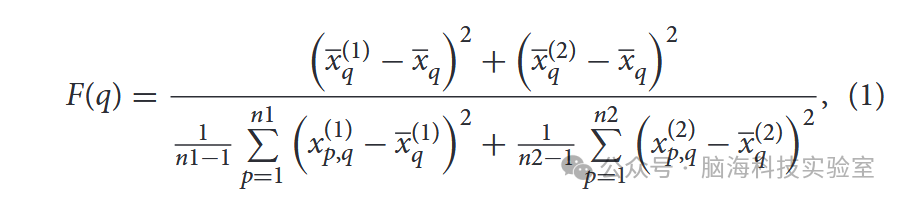

根据费舍尔标准独立计算每个特征的分数。随后,选择了排名最高的前k个特征。第q个特征的费舍尔分数定义如下: